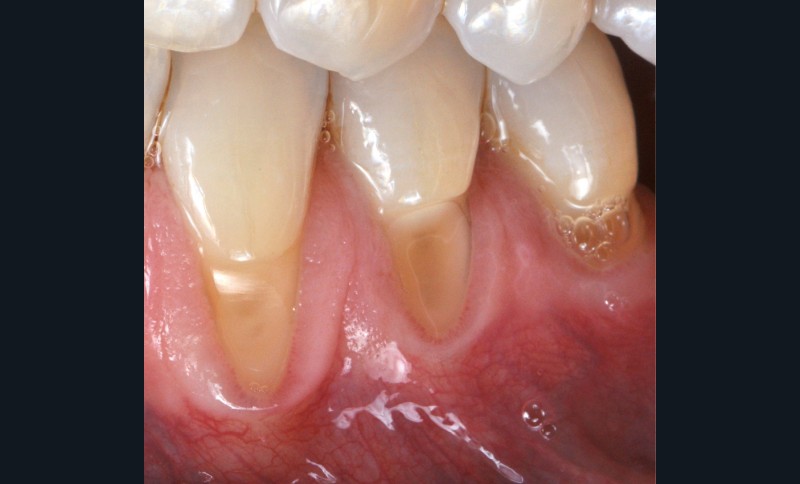

Zuchelli et coll. [1] définissent quatre causes à l’origine des récessions gingivales à la suite d’une déhiscence osseuse : les causes traumatiques (fig. 1) par le brossage, le surcontour prothétique, les piercings ; les causes bactériennes (fig. 2) liées à une inflammation marginale ; les causes virales par le virus de l’herpès simple ; et les origines mixtes, à savoir traumatiques et bactériennes (fig. 3). Le diagnostic de récession liée à la plaque dentaire dépend de la présence de dépôts tartriques et/ou d’inflammation des tissus environnant les zones exposées. En présence d’une origine mixte, la récession est d’abord initiée par un brossage traumatisant, rendant la surface radiculaire hypersensible ou irrégulière, ayant une répercussion négative sur le brossage et l’accessibilité à l’hygiène.